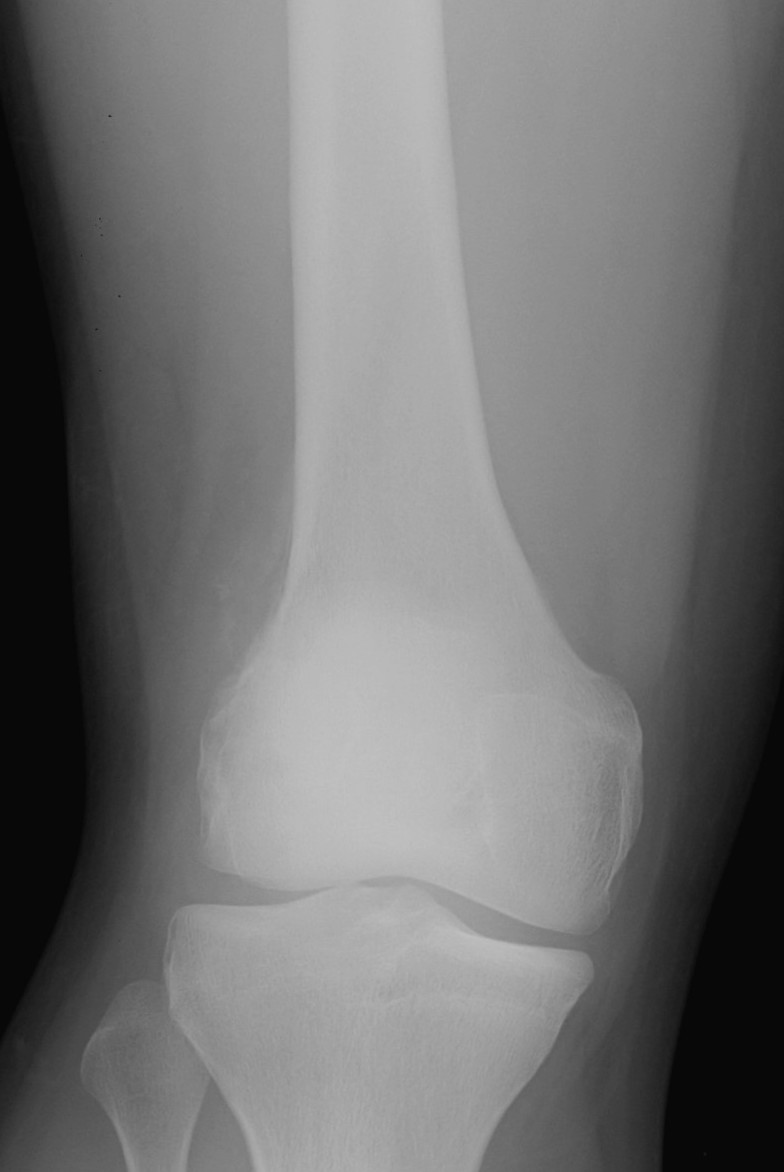

Onion skinning lateral distal femur